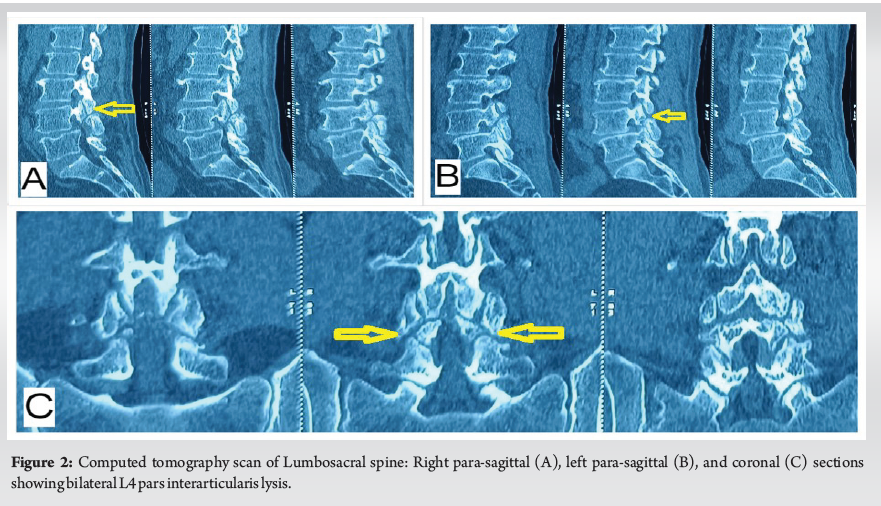

Hemorrhagic Ligamentum Flavum Cyst in the Adjacent Level of Lytic Spondylolisthesis – A Case of Diagnostic and Therapeutic Dilemma

Bibhudendu Mohapatra , Nirdesh Hiremagalur Jagadeesh , Mayukh Guha , Anita Agarwal , Jomin George , T Fazal Rehman ………………………………p.41-46